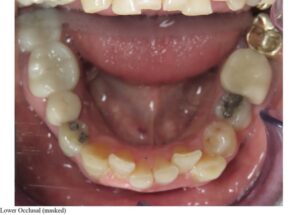

Case 1 – No attachments, lower treatment only (extraction LL2)

| Initial | 6-month progress, 25 aligners |

![]() | ![]() |